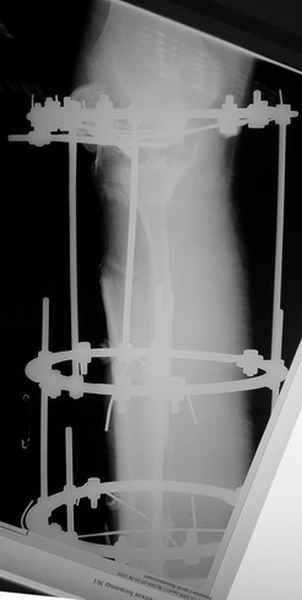

Пациент В. 53 лет, травма в феврале 2009. ДЗ. Открытый оскольчатый перелом нижней трети голени. При боли поступлении выполено ПХО, аппарат Илизарова. В последующем проводили ВХО, резекция костных отломков, укорочение 6 см, рана зажила. Была выполнена остеотомия большеберцовой кости в проксимальном отделе, резекция. Производилось тракция. На последних рентгенограммах выявлено, что одновременно с "выращиванием" регенерата произошло низведение надколенника на длину выращенного регенерата. Клинически: активное разгибание сохранено, объем движений в колене 180-110 градусов. Черными стрелками обозначен верхний край надколенника с одной и с другой стороны. Красная стрелка обозначает пальпируемую связку надколенника. Причина - остеотомия выше места прикрепления связки надколенника. Вопрос: была ли у кого подобная ситуация? Что делать? При первом обдумывании приходит решение: отсечение места прикрепления связки надколенника с костным блоком, перемещение на "правильное" место, укорочение сухожилия четырехглавой мышцы.

По снимкам - плотность регенерата хорошая, сложностей с фиксацией в него костного "основания" быть не должно.